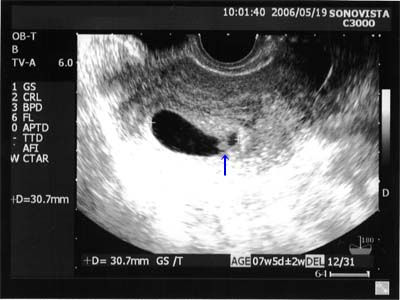

| 2006年7月7日(金) |

| 13w5d 4ヶ月検診を兼ねた助産師外来 寝てるようであまり動いてくれなくて心配したけど、 上げてた手(1枚目)を下に下げて(2枚目)動いてくれました。 助産師さんだったからか、大きさは測ってくれなかったのでわかりません。 |